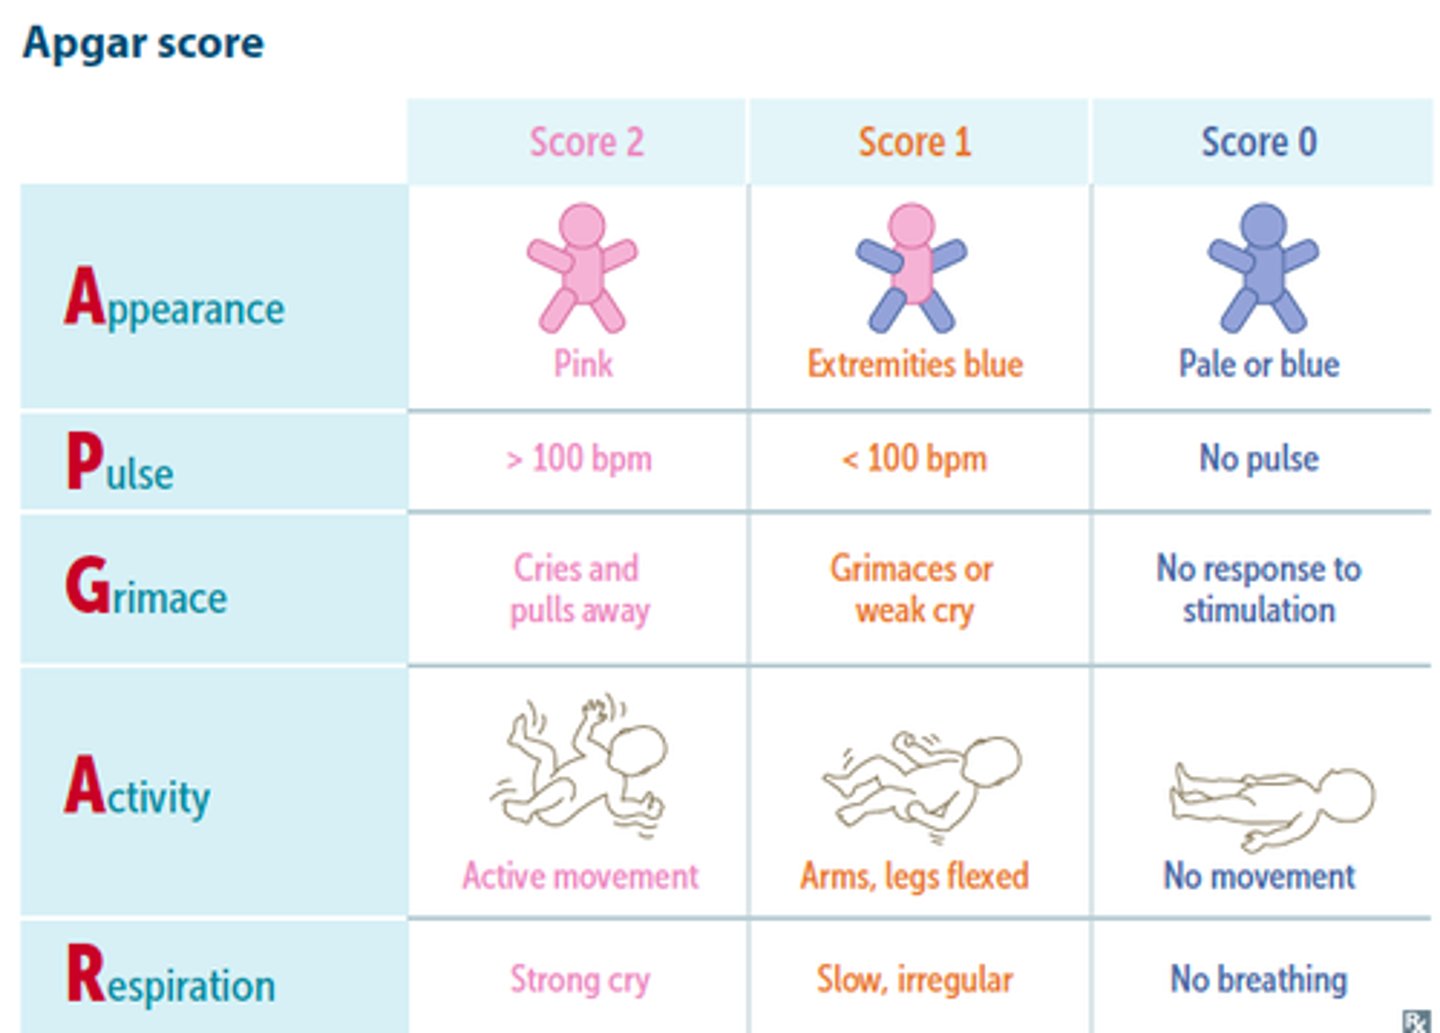

Apgar score

Appearance

Pulse

Grimace

Activity

Respiration

> 5 @ 1 min & 8-10 @ 5 min = normal

What APGAR score at 1 minute requires immediate resuscitation?

< 4

What APGAR score @ 5 mins indicates increased risk of CNS/Cardiac dysfunction?

< 7